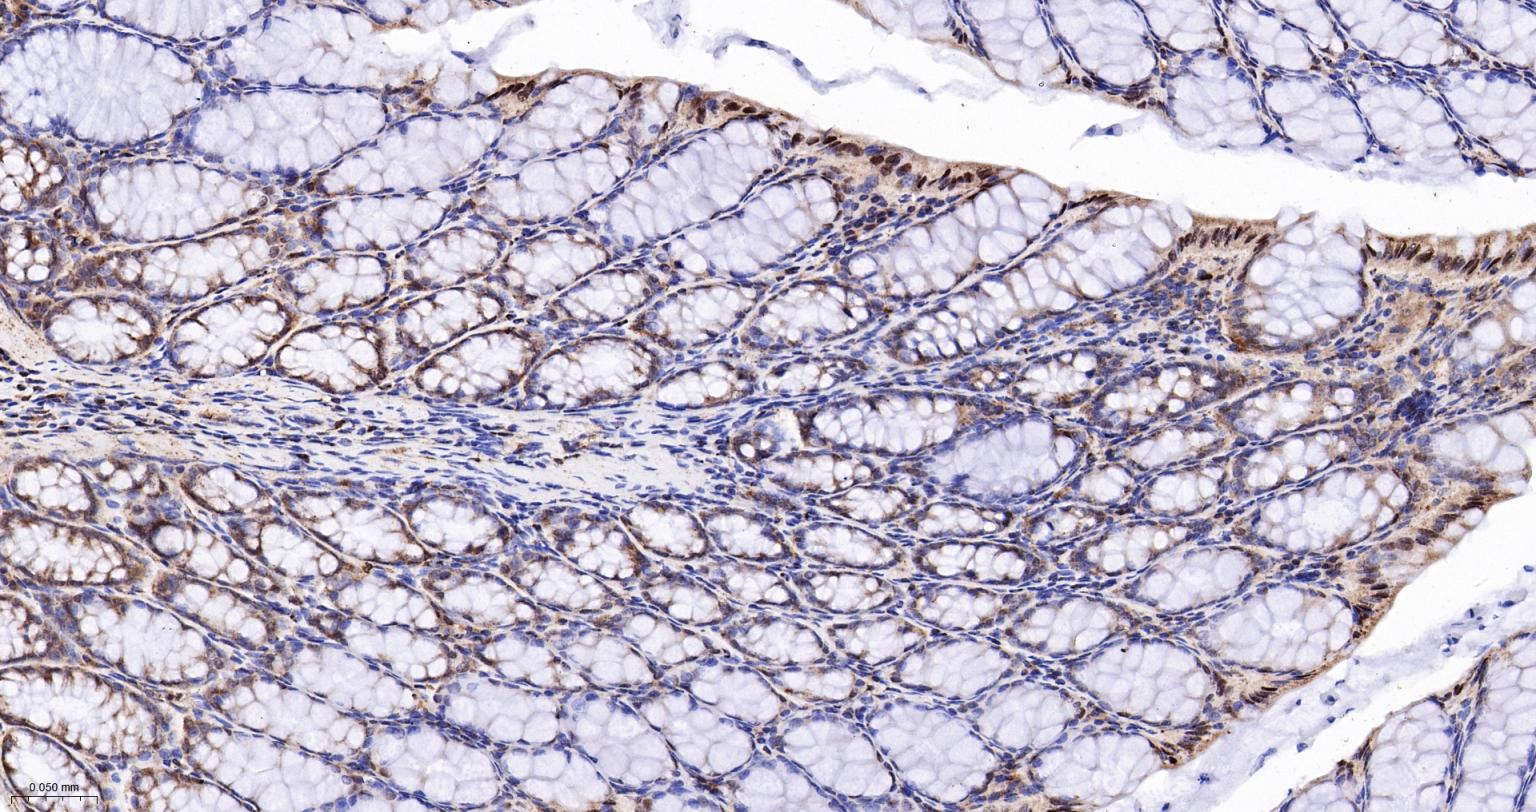

Paraformaldehyde-fixed, paraffin embedded Human Colon; Antigen retrieval by boiling in sodium citrate buffer (pH6.0) for 15 min; The section was incubated with IMPDH2 Monoclonal Antibody, Unconjugated (bsm-61947R) at 1:200 overnight at 4°C, followed by conjugation to the bs-0295G-HRP and DAB (C-0010) staining.